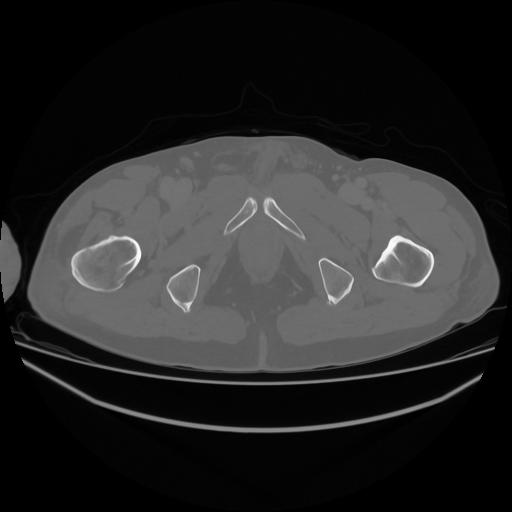

5 CUERPO,CE,Vol,1.0,CUERPO,,